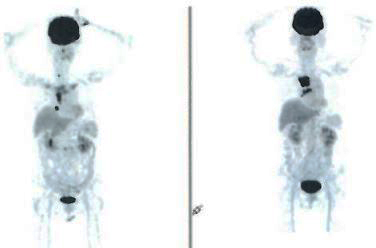

Sebelum memulai kemoterapi, pemindaian PET dilakukan. Laporan pemindaian PET tanggal 9 September 2021 menunjukkan:

• Akumulasi pelacak fokus terlihat di anterior bagian ketiga duodenum (0,8 x 1,0 x 0,9 cm). Kelenjar getah bening avid FDG ini kemungkinan mewakili metastasis.

• Ground glass opacity terlihat di lobus kiri bawah paru.

• Tidak ada bukti metastasis ke otak, kelenjar getah bening, leher, toraks, mediastinum, panggul, tiroid, paru, lambung, hati, pankreas, limpa, adrenal, dan tulang.

Perawatan kemo selesai pada April 2020. Pemindaian PET yang dilakukan pada 7 April 2022 menunjukkan:

• Dibandingkan dengan pemindaian yang dilakukan pada 9 September 2021, pemindaian saat ini menunjukkan respons metabolik yang lengkap terhadap pengobatan. Masalah terpecahkan!

• Patchy ground glass opacity yang terlihat pada lobus kiri bawah paru tampak tidak berubah.

• Tidak ada bukti lesi avid FDG terlihat di bagian lain dari tubuh.

Enam bulan kemudian, Harry melakukan pemindaian PET lagi. Laporan PET scan tanggal 13 Oktober 2022 menunjukkan:

• Patchy ground glass/consolidative opacity terlihat di lobus kiri bawah paru membesar.

• Opasitas nodular tambal sulam baru terlihat di segmen anterior lobus kanan atas.